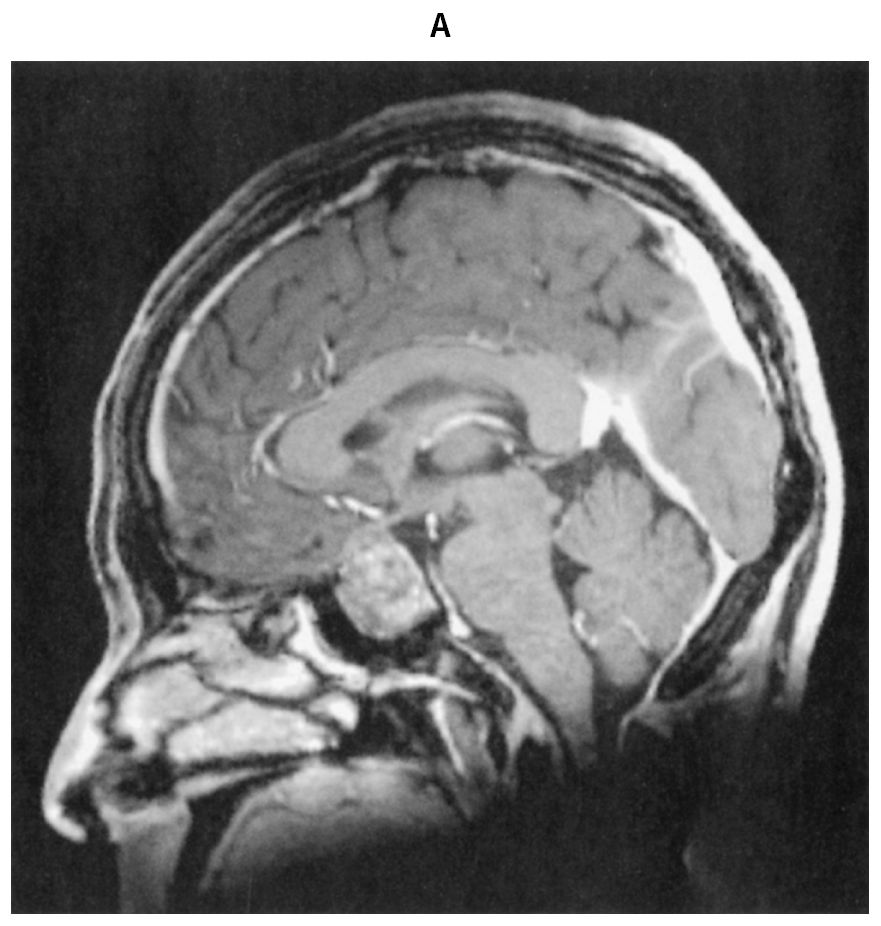

54歳の男性。口腔内の違和感を主訴に来院した。2年前から口唇の肥厚と下顎の突出を自覚し,その後,靴のサイズが約1cm大きくなり,指輪が外れなくなった。既往歴に高血圧症があり内服治療中である。また,睡眠時無呼吸症候群で通院中である。意識は清明。身長162cm,体重72kg。体温36.5℃。脈拍96/分,整。血圧120/90mmHg。矯正視力は右1.5左0.2。顔面は,眉弓突出,口唇肥大および下顎突出を認め,口腔内は舌の腫大を認める。血液所見:赤血球366万,白血球4,200,血小板20万。血液生化学所見:総蛋白7.6g/dL,アルブミン4.4g/dL,総ビリルビン0.6mg/dL,AST 18U/L,ALT 15U/L,尿素窒素22mg/dL,クレアチニン0.7mg/dL,空腹時血糖111mg/dL,HbA1c 6.3%(基準4.9~6.0),Na 140mEq/L,K 4.1mEq/L,Cl 104mEq/L。頭部造影MRIのT1強調矢状断像(A)と頭部単純MRIのT2強調冠状断像(B)とを下に示す。